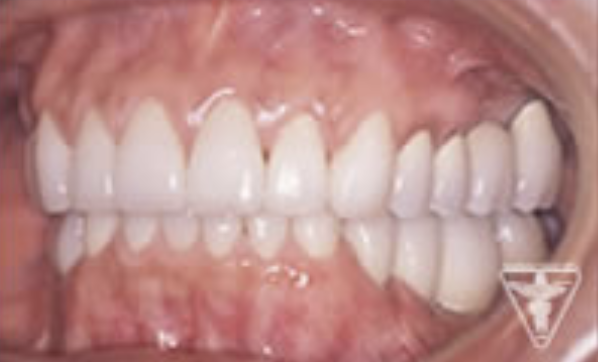

治療後

かみ合わせの深さを改善し、左下の骨を作り人工歯根で再構築しました。

前歯は、患者さんの希望でフルセラミックで対応しました。

「良く噛めて、自信をもって笑顔になれる。」と評価をいただきました。